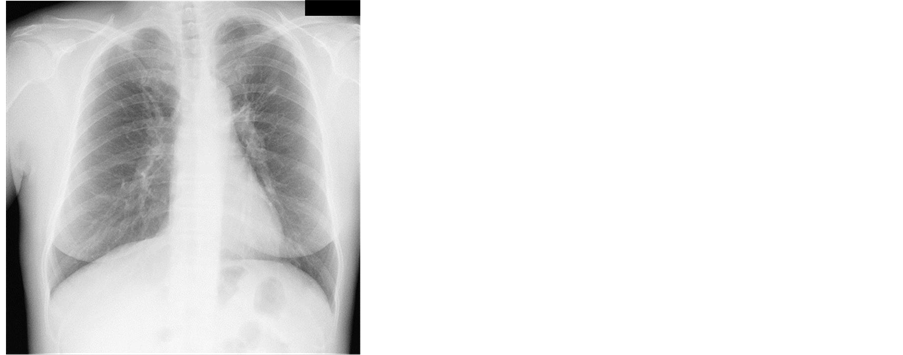

Case 1: A53-year-old woman visited our hospital due to an abnormal chest shadow. She had no underlying diseases and no smoking history. There were no abnormal physical findings on admission. There were no abnormal laboratory findings in the peripheral blood or chemical screening, but Quanti FERON TB-Gold (QFT-G) was also positive (ESAT-6: 0.92 IU/ml). Chest radiographs showed nodular and linear shadows in the left upper lung field (Figure 1). Chest CT showed nodular and linear shadows with bronchiectasis and small cavities in the left upper lobe and lingula (Figure 2). Because she could not expectorate sputum and we could not rule out pulmonary tuberculosis completely, we performed bronchoscopy. The culture of bronchoscopic specimens generated acid-fast bacilli and the result of DNA-DNA hybridization (DDH) method identified M. kansasii. Finally, she was diagnosed with pulmonary M. kansasii disease. Afterwards, she was treated with combined chemotherapy using INH, RFP, and EB for one year and abnormal chest shadows improved following the combined chemotherapy.

Figure 1. Chest radiograph s showed nodular and linear shadows in the left upper field.